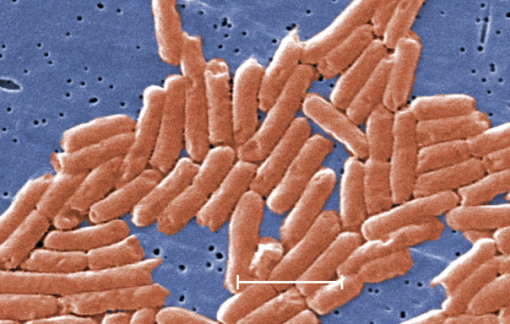

Một loài vi khuẩn chưa từng được biết đến vừa được phát hiện có liên quan đến Noma - căn bệnh 'ăn mòn khuôn mặt' ở trẻ bị suy dinh dưỡng.